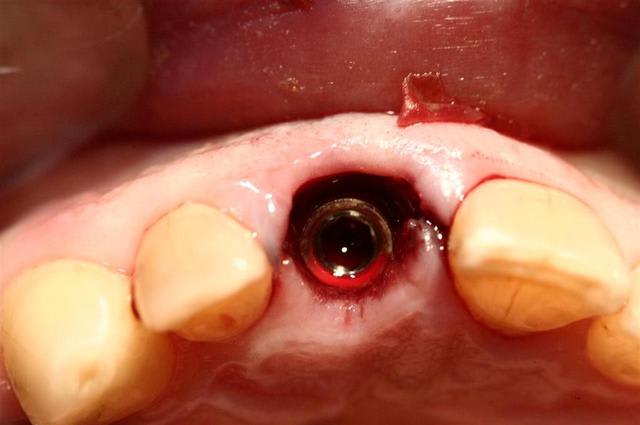

c'est posé; allez y

le petit trou en palatin de ton moignon, c'est pour quoi?

utilises-tu des piliers de cicatrisation évasés pour préparer à minima ton émergence gingivale?

c'est tout simplement un faux moignon "droit" en titane idi

ils ont tous ce petit trou que j'utilise parfois pour l'enlever, lors des essais

Quel que soit le diamètre de 2,8 à 3,7 le col fait 4mm, cela simplifie la prothèse (peut être trop)

L'axe est effectivement un peu vestibulaire